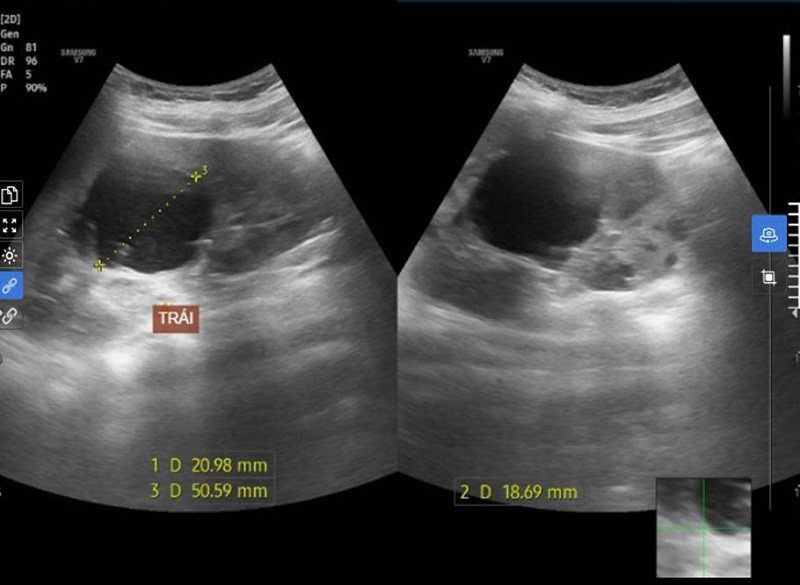

Khi khám, bác sĩ phát hiện hình ảnh siêu âm bụng phát hiện thận đa nang hai bên (thận trái > 7 nang, thận phải >10 nang), kích thước thận to, chưa có suy giảm chức năng thận. Bác sĩ tiếp tục tư vấn bệnh nhân làm thêm các xét nghiệm tầm soát biểu hiện ngoài thận của bệnh thận đa nang như: Siêu âm bụng (nang gan, nang tụy...), điện tim, siêu âm tim (bệnh van tim, bệnh mạch vành...).

Dựa vào kết quả lâm sàng và cận lâm sàng, bác sĩ chẩn đoán A. mắc bệnh thận mạn giai đoạn 1 và thận đa nang chưa có biểu hiện tại thận cũng như ngoài thận.